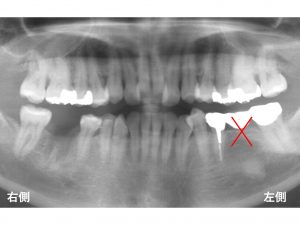

下顎左側の奥から2番目が欠損しています。

この患者様も歯を削らずに、

義歯のような取り外し式の治療ではない

インプラント治療をご希望されました。

以下が先日行ったインプラント治療後です。